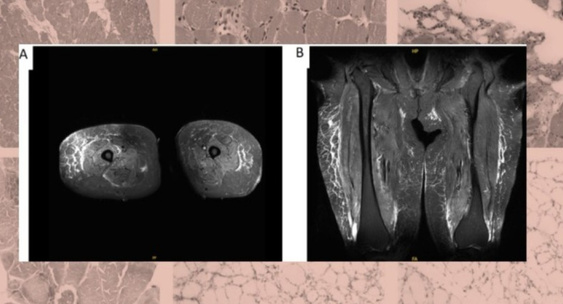

Американские врачи описали случай иммуноопосредованной некротизирующей миопатии у пожилой пациентки, которая однократно применила семаглутид.N + 1

В течение четырех месяцев у нее наблюдались нарушения голоса и глотания, а также слабость мышц.N + 1